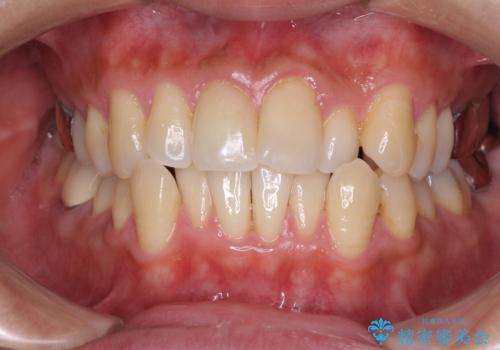

受け口傾向の咬み合わせ 前歯のデコボコをワイヤー矯正で素早く改善

- 前歯の見た目を気にして来院された患者様です。

ワイヤー矯正でもマウスピース矯正でも対応可能とお伝えし、非常に悩まれていましたが、2年後に転勤の可能性が高いとのことで、治療終了までの期間を想定しやすいワイヤー矯正にて治療を行うこととしました。

この患者様もクロスバイトはあっという間に改善され、1年強で速やかに治療を終えることができました。